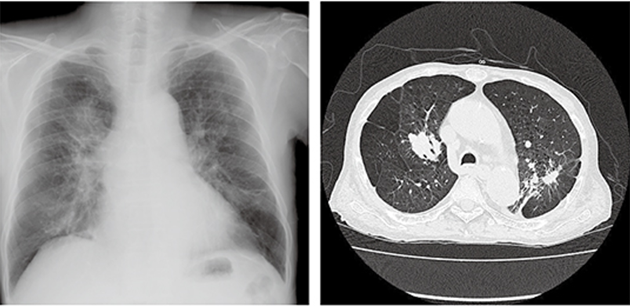

一般檢查以X射線為主,并結(jié)合患者職業(yè)情況予以判斷。根據(jù)診斷標準,塵肺病一般不難確診。但有時候小孩子長期跟父母生活在煤場或者發(fā)電廠等嚴重大氣污染的地區(qū),因為并沒有直接從事相關(guān)工作,在診斷的時候容易被誤診為肺結(jié)核。

患者一旦確診為塵肺病,應(yīng)立即遠離之前的工作環(huán)境。粉塵環(huán)境作業(yè)的高危人群應(yīng)該嚴格遵守防護要求以及定期檢查肺功能。